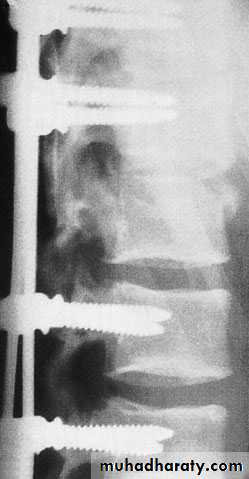

Axial compression or burst injury

Severe axial compression may ‘explode’ the vertebral body, causing failure of both the anterior and the middle columns. The posterior column is usually, but notalways, undamagedAnteroposterior x-rays may show

spreading of the vertebral body with an increase of the interpedicular distance

Posterior displacement of bone into the

spinal canal (retropulsion) is difficult to see on the plain lateral radiograph; a CT is essential.